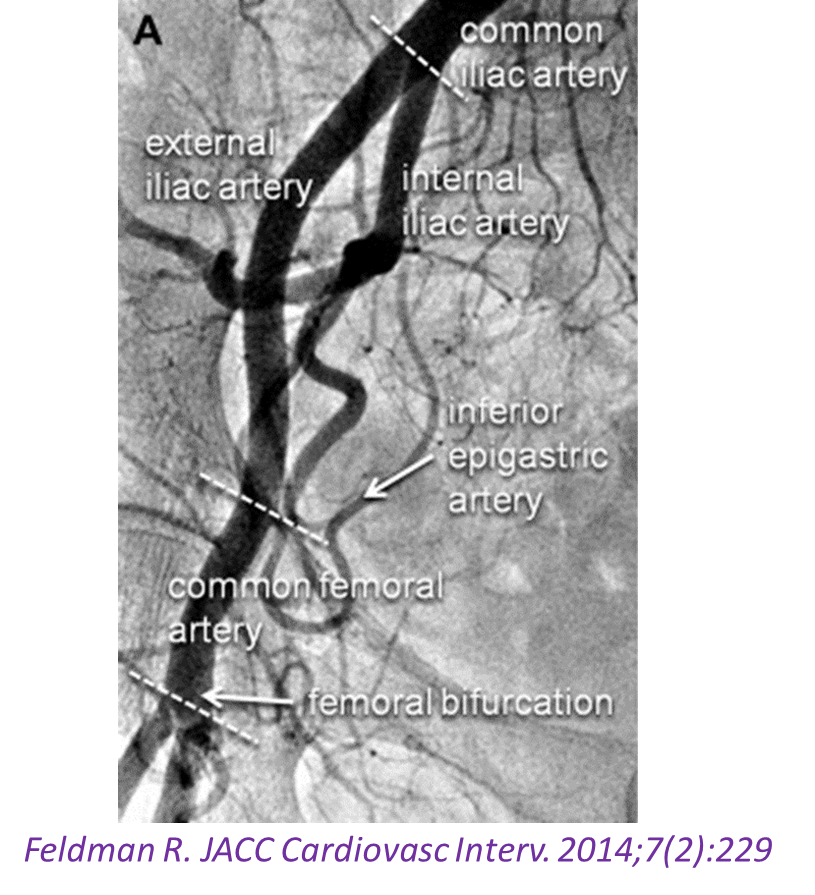

股总动脉(Common Femoral Artery, CFA)是连接髂动脉与下肢远端血管的关键枢纽,解剖位置表浅、血流动力学复杂,既易受动脉粥样硬化影响,也常因医源性操作(如穿刺)引发并发症。其病变类型主要包括扩张性病变(如动脉瘤、假性动脉瘤)和闭塞性病变(如斑块闭塞、血栓形成)。尽管腔内技术日益普及,但现有循证医学证据仍支持开放手术为处理CFA病变的首选方法,尤其在涉及股深动脉(Profunda femoris artery)保护时更为关键。

正如欧洲血管外科学会前主席France Moll所言:“We work on SFA, but live on Profunda.” —— 股浅动脉(SFA)闭塞可能仅导致跛行,而股深动脉一旦丧失,则截肢风险显著升高。